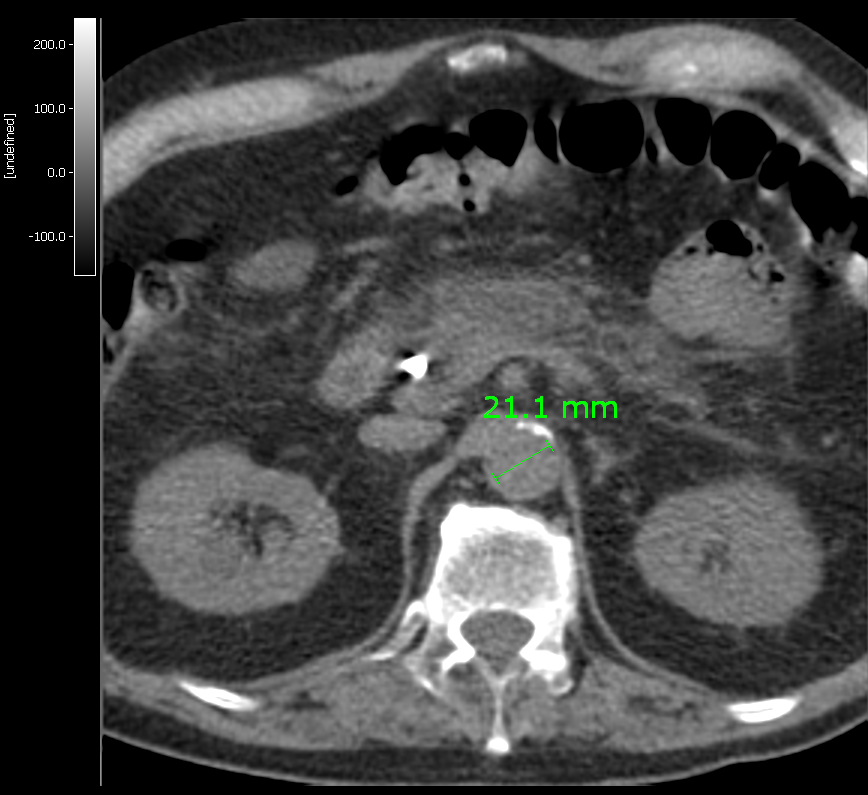

If a CT image is available for the study, it should be used to asses the diameter of aorta. For example in Vinci you can use measure tool from tool box (see figure1). Measure diameter inside the artery wall, DO NOT include the walls. Make sure that the diameter is not varying too much between planes and write down the number of the plane which was used in the measuring. After that, call program eabaort with option -d

eabaort -d=22 -F=6.3 s06678dy1_mrp.img 11 14 s06678ab.dat

You still need to know the FWHM value. When you give the plane numbers, you should include the one where diameter was measured and choose planes around it.

CT_aorta.png Figure 1. (Click to enlarge)